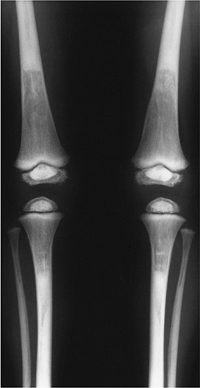

FIGURE 15-8

Osteopetrosis intermediate. AP radiographs of the tibia and femora showing bone sclerosis with bone-within-a-bone appearance in the epiphyses. |